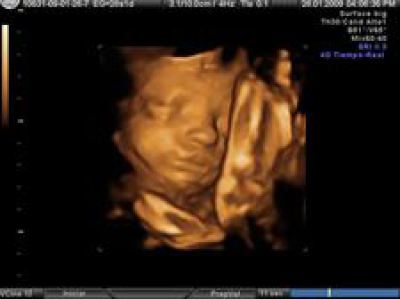

En virtud del párrafo 52 del informe, el más polémico sobre los derechos de salud sexual y reproductiva y el aborto que ha salido finalmente adelante por 404 votos a favor, 250 en contra y 44 abstenciones, la Eurocámara llama a la Comisión "a asistir a los Estados miembros a garantizar una elevada calidad, apropiada geográficamente y servicios accesibles fácilmente en las áreas de los derechos de la salud sexual y reproductiva y un aborto seguro y legal y la contracepción". Otro apartado del informe defiende además que "la mujer debe tener derecho a controlar su propio cuerpo" y se defiende promover cursos sobre educación sexual en las escuelas.

El aborto es la mayor causa de muerte con gran diferencia: Llevamos más de 25 millones de abortos este año

Hay cosas que suceden todos los días y, por ello, no son noticia, pero deberían serlo. Hoy se acabará con la vida de unos doscientos mil niños no nacidos, con el beneplácito de gobiernos, parlamentos, médicos e incluso de sus padres. https://www.infocatolica.com/?t=noticia&cod=52974